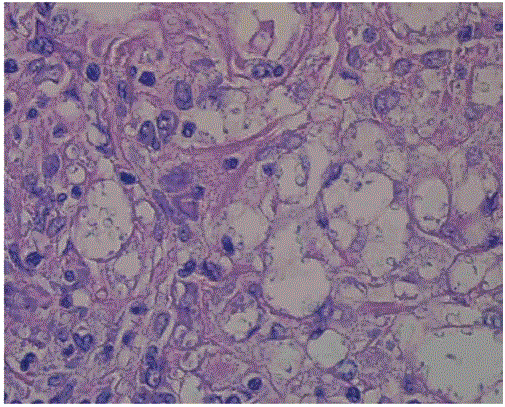

此外,进行胸水抽吸。液体为渗出物,细菌培养阴性。抗酸杆菌(AFB)涂片阴性,需要MTB/利福平基因专家和培养。因为肺结核在病人居住的城市是地方病,所以在结果出来之前进行了胸椎引导活检,并开始了标准的四种方案治疗。入院一周后,病人的发烧有所好转。总体外观:面罩样,下肢肌阵挛运动。神经系统检查除缓慢的眼跳运动外,未见明显颅神经异常。运动检查显示双上肢张力增加,肌肉群力量4/5。铅管硬度与正常动力和左上走种植,持续双侧踝关节阵挛,步态和协调性难以评估。进一步行脑部影像学检查,脑CT示室周T2弥漫性增高,伴多处离散、融合、非增强的变大小信号异常,双侧基底节区可见少量小环状强化病变, and the right centrum and left temporal cortical enhancing focus was noted as well as per figure 5. Lung biopsy was positive for granuloma and fungal elements look like yeast and negative for culture. Positive staining for both Periodic Acid-Schiff (PAS) stain and Gomori Methenamine Silver (GMS) stain. The latter is suggestive of histoplasmosis as per figures 6-8.

图6:格罗考特甲基胺银染色可以很好地显示黑色的真菌元素(×100)。

图7:粘稠的鲜红色蒴果,粘卡明染色(×100)。

图8:格罗考特甲基胺银染色可以很好地显示黑色的真菌元素(×100)。